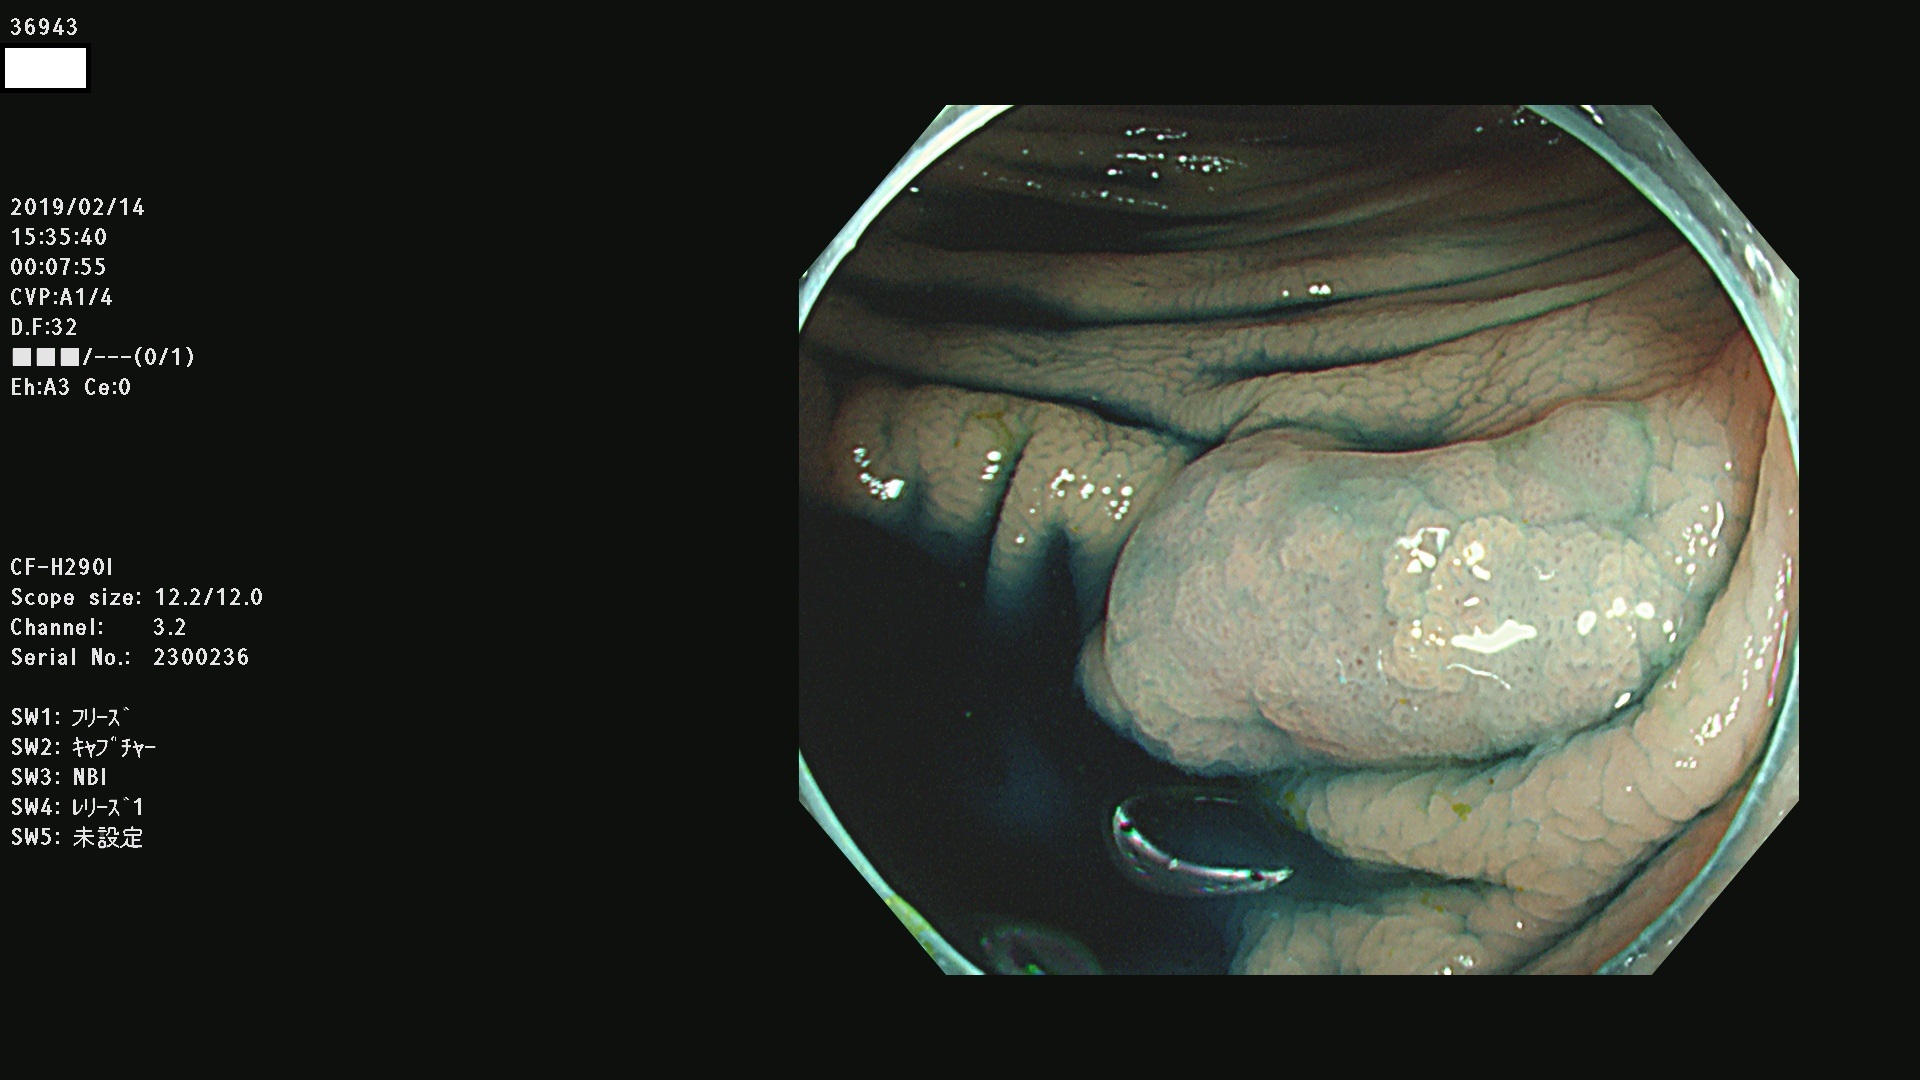

発見困難で危険性の高い平坦型病変(上記100名より抽出) ![]()